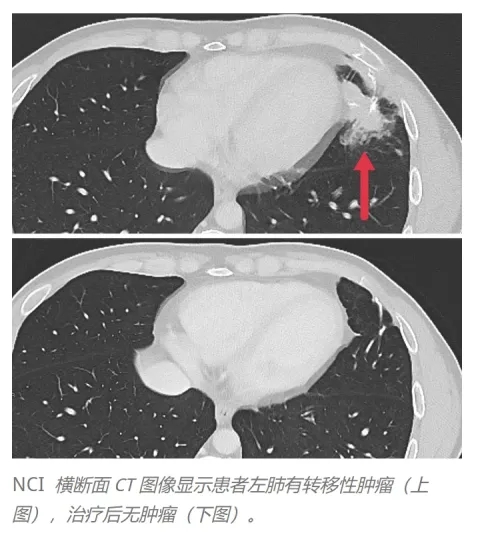

结果显示:按RECIST标准评估,3例患者出现客观临床反应,肝脏、肺及淋巴结的转移性肿瘤均消退,缓解持续4~7个月。

下图为一例典型患者接受TCR-T治疗前后左肺转移灶的CT图像对比:治疗前,患者左肺存在转移性肿瘤;治疗后,转移灶明显消退(详见下图)。

▲图源“nature”,版权归原作者所有,如无意中侵犯了知识产权,请联系我们删除